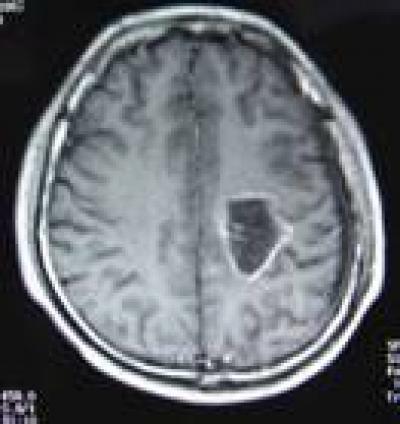

This is an MRI scan showing increased tumor necrosis and surrounding tissue with no obvious enhancement at 12 months after hyperthermia.

(Photo Credit: Neural Regeneration Research)